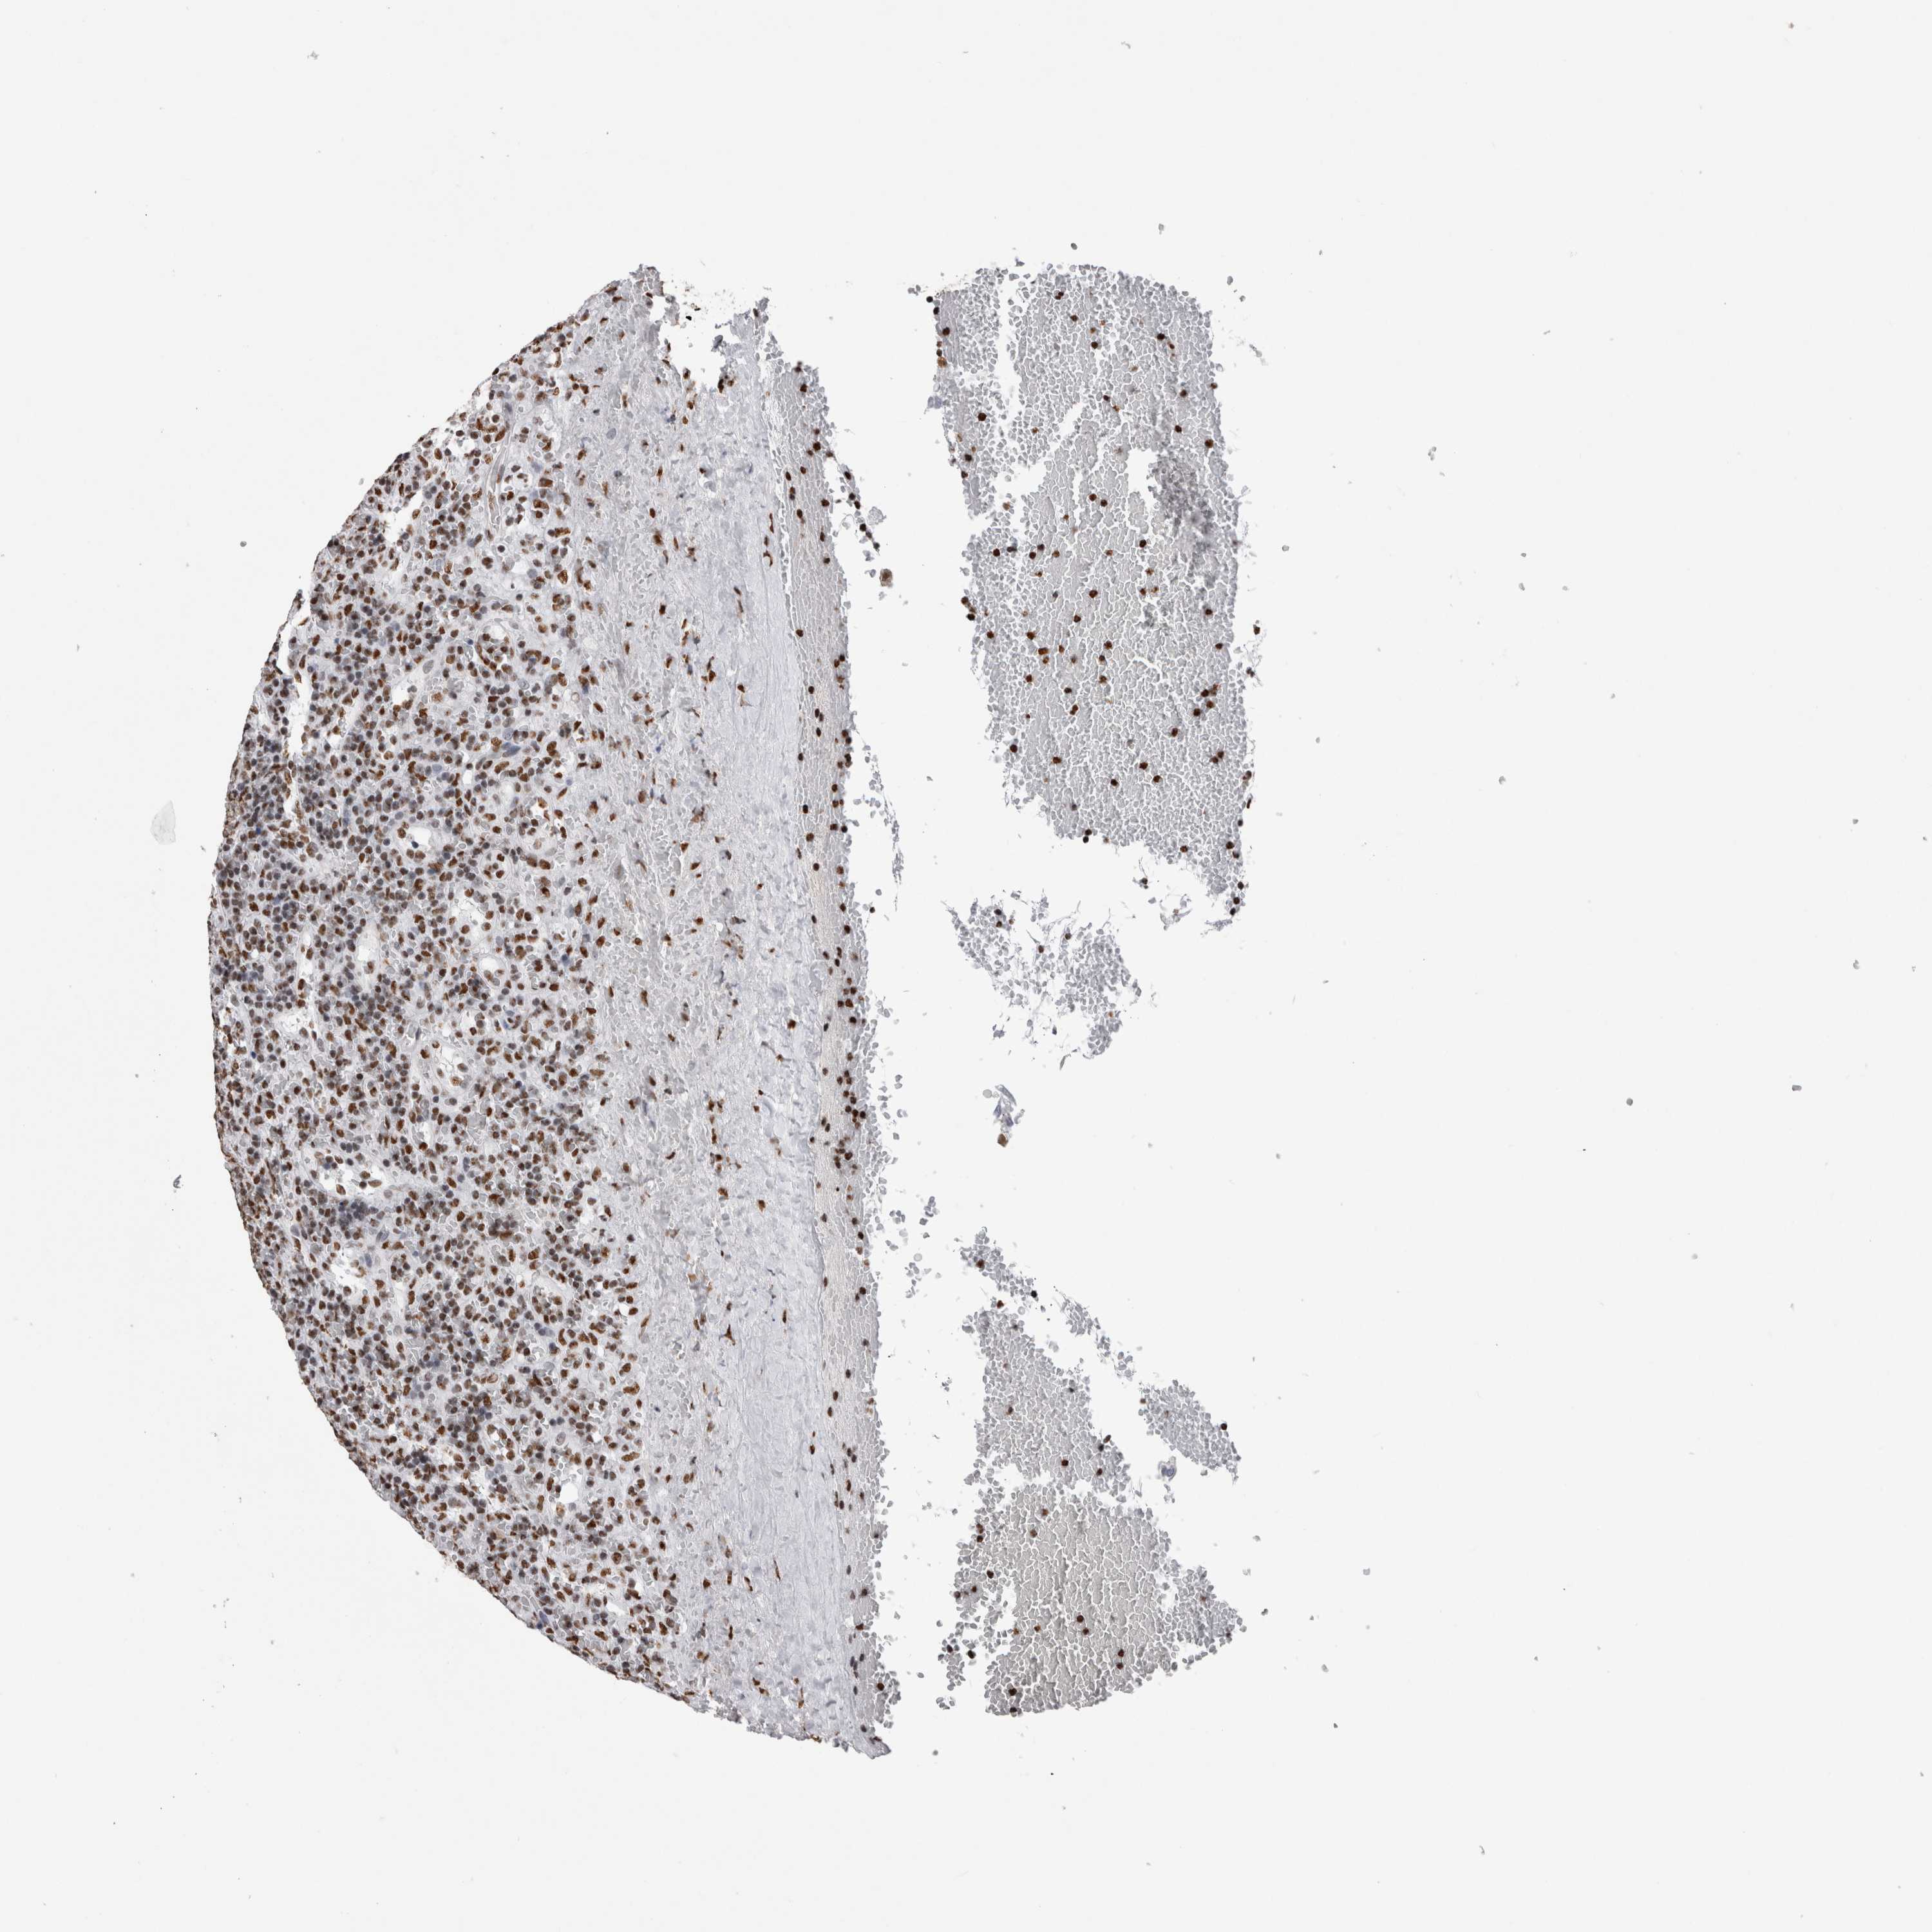

LYMPHOMA - Protein expressioni

A mouse-over function shows sample information and annotation data. Click on an image to view it in a full screen mode. Samples can be filtered based on level of antibody staining by selecting one or several of the following categories: high, medium, low and not detected. The assay and annotation is described here.

Antibody stainingi

Antibody staining in the annotated cell types in the current human tissue is reported as not detected, low, medium, or high, based on conventional immunohistochemistry profiling in selected tissues. This score is based on the combination of the staining intensity and fraction of stained cells.

Each image is clickable and will lead to virtual microscopy that enables deeper exploration of all samples and also displays staining intensity scores, fraction scores and subcellular localization as well as patient and tissue information for each sample.

Antibody HPA026558

Staining

High

Medium

Low

Not detected

Intensity

Strong

Moderate

Weak

Negative

Quantity

>75%

75%-25%

<25%

None

Location

Nuclear

Cytoplasmic/membranous

Cytoplasmic/membranous,nuclear

Hodgkin's disease, NOS

Malignant lymphoma, non-Hodgkin's type, High grade

Malignant lymphoma, non-Hodgkin's type, Low grade